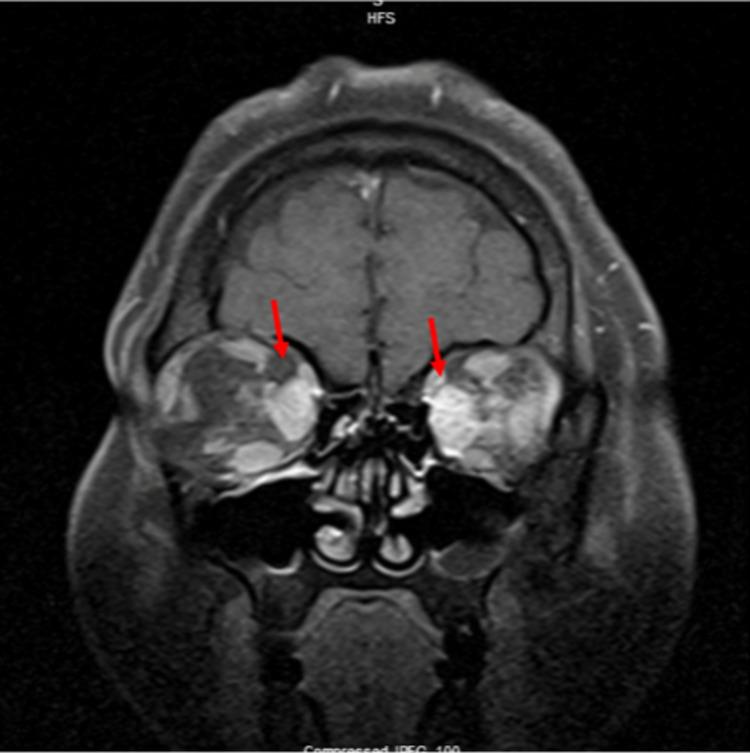

Thyroid eye disease (TED), also known as Graves' orbitopathy or ophthalmopathy (GO) or Graves' eye disease, is an autoimmune condition of the retroocular tissues associated with Graves' disease. In isolated GO, the patient can present without thyroid hormone dysfunction or systemic symptoms of Graves' disease, in which case it is called euthyroid Graves' ophthalmopathy (EGO). It is very rare for this condition to have negative thyroid-stimulating hormone receptor (TSHR) autoantibodies, and we present such a rare case of a young female, who had progressive bilateral vision loss, intermittent left-sided retroocular headache, and severe bilateral proptosis. The patient was diagnosed with EGO based on multidisciplinary consults, diagnostic orbital magnetic resonance imaging (MRI) results, and a good response to treatment with intravenous steroids. Later, the patient was followed as an outpatient and treated with thyroid orbitopathy-specific immunotherapy with teprotumumab. The patient's response to teprotumumab was excellent and caused significant improvement in visual acuity, proptosis, and chemosis. This adds valuable literature to the medical field and gives insight to clinicians to consider the diagnosis of GO even with seronegative TSHR autoantibodies and euthyroid hormone status. It also adds to the understanding of the complex pathophysiology of this rare condition.